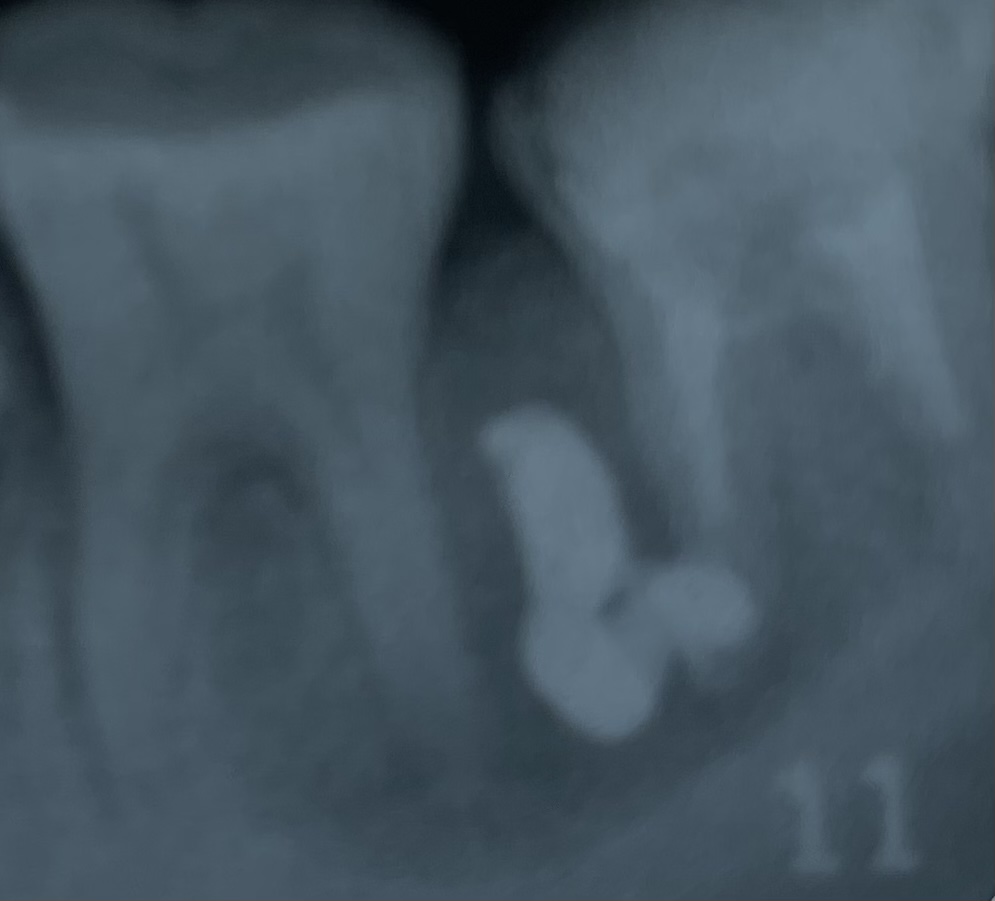

病巣が治ったかどうかは、エックス線写真の比較でしか判定出来ません。

また、病巣が治癒したのち、新しい骨組織(こつそしき)が完成し、エックス線写真で認められるようになるためには、半年程度かかるのです。

上の写真たちが、令和4年4月のものでした。

つい先日(現在、令和4年10月です)、半年後のエックス線写真を撮影し、治癒の確認を行いました。

それが下の写真です。

新しい骨も順調に形成されていて、

治療は今のところうまくいっているようです。